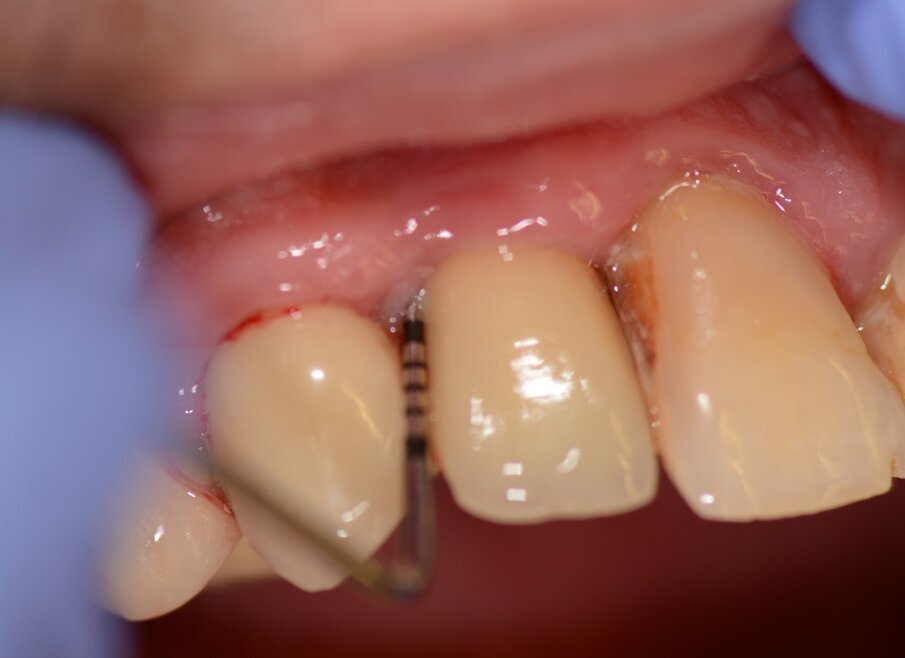

Case 1 was a patient who presented with deep pockets (9 mm), bleeding on probing and visible purulent effusion (Figs. 1–7) and was treated with a non-surgical protocol.

Fig. 2: Pocket depth measurements.

Fig. 3: Bleeding on probing.